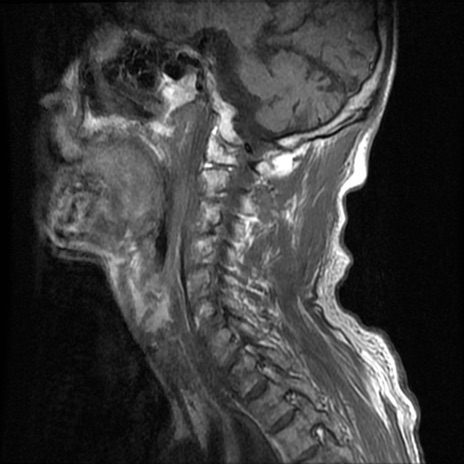

症例46 頚椎MRI T1WI(矢状断像)

【症例】80歳代男性

【主訴】両側頚部〜上肢のしびれ

【現病歴】昨日、自宅内で転倒、その後より上記症状あり。意識障害なし。

【身体所見】両側上肢のallodynia(熱痛覚過敏)あり。MMTおよびDTRは正確な所見取れず。両上肢の挙上はなんとか可能。

異常所見と診断は?

頚椎MRI

T2WI(矢状断像)